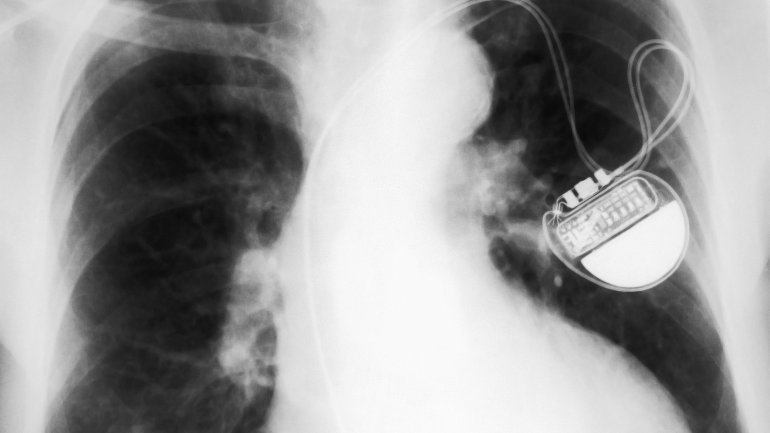

Bei einem Herzschrittmacher handelt es sich um ein kleines elektronisches Gerät mit einem Impulsgenerator, das etwa die Größe einer Streichholzschachtel hat. Es wird meist unterhalb des Schlüsselbeins unter die Haut implantiert und über eine oder mehrere Elektroden mit dem Herz verbunden. Diese messen kontinuierlich den Herzschlag und leiten die Information an den Impulsgenerator weiter. Dieser speichert und vergleicht die Signale der selbstständigen Herzaktivität und löst nur dann einen Impuls aus, wenn sich der Herzschlag verlangsamt. So bringt er das Herz wieder in den richtigen Takt. Zudem passt er den Herzschlag der körperlichen Belastung an, sodass Aktivitäten wie Radfahren oder Treppensteigen in der Regel wieder beschwerdefrei möglich sind.

Heutzutage implantiert der*die Kardiolog*in den Herzschrittmacher innerhalb einer Stunde unter lokaler Betäubung . Meist bildet der*die Kardiolog*in durch einen Hautschnitt unterhalb des Schlüsselbeins eine kleine Tasche, in der der Herzschrittmacher später seinen Platz findet. Zuvor werden die Elektroden soweit zum Bestimmungsort, also den rechten Vorhof, die rechte Herzkammer oder beides, vorgeschoben, bis sie das Muskelgewebe berühren. Dies lässt sich während des Eingriffs mittels eines Röntgengeräts überprüfen.

Sobald die Elektroden richtig sitzen, werden sie an den Impulsgeber angeschlossen, das Gerät auf die Bedürfnisse des*der Patient*in programmiert und auf seine einwandfreie Funktion getestet. Dann wird der Herzschrittmacher in der Hauttasche platziert und die Wunde schließlich vernäht und mit einem Verband versorgt. Manche Patient*innen können das Krankenhaus noch am selben Tag verlassen, in der Regel bleibt man aber zur Beobachtung über Nacht. Die Fäden können nach ungefähr zehn Tagen gezogen werden. Die erste Nachsorgeuntersuchung steht in der Regel nach drei Monaten an.